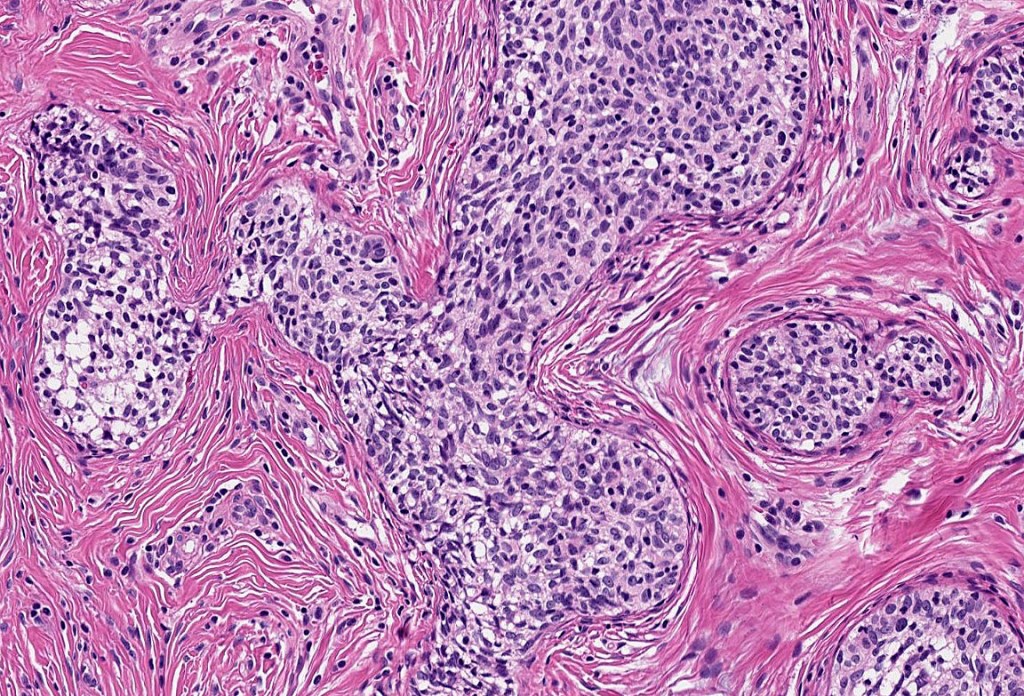

Histological features

•Dermal nodule, rarely extends into subcutaneous fat

•Irregular lobules of epithelial cells embedded in a dense fibrous stroma

•Peripheral rim of darkly staining basaloid cells surrounding larger pale staining cells with vesicular nuclei with often prominent eosinophilic nucleoli

•Central cells PAS positive (glycogen)

•No pleomorphism or mitotic activity

•No retraction artifact or stromal mucin

•Admixed lymphocytes (an obligatory feature)

•Germinal centers sometimes present